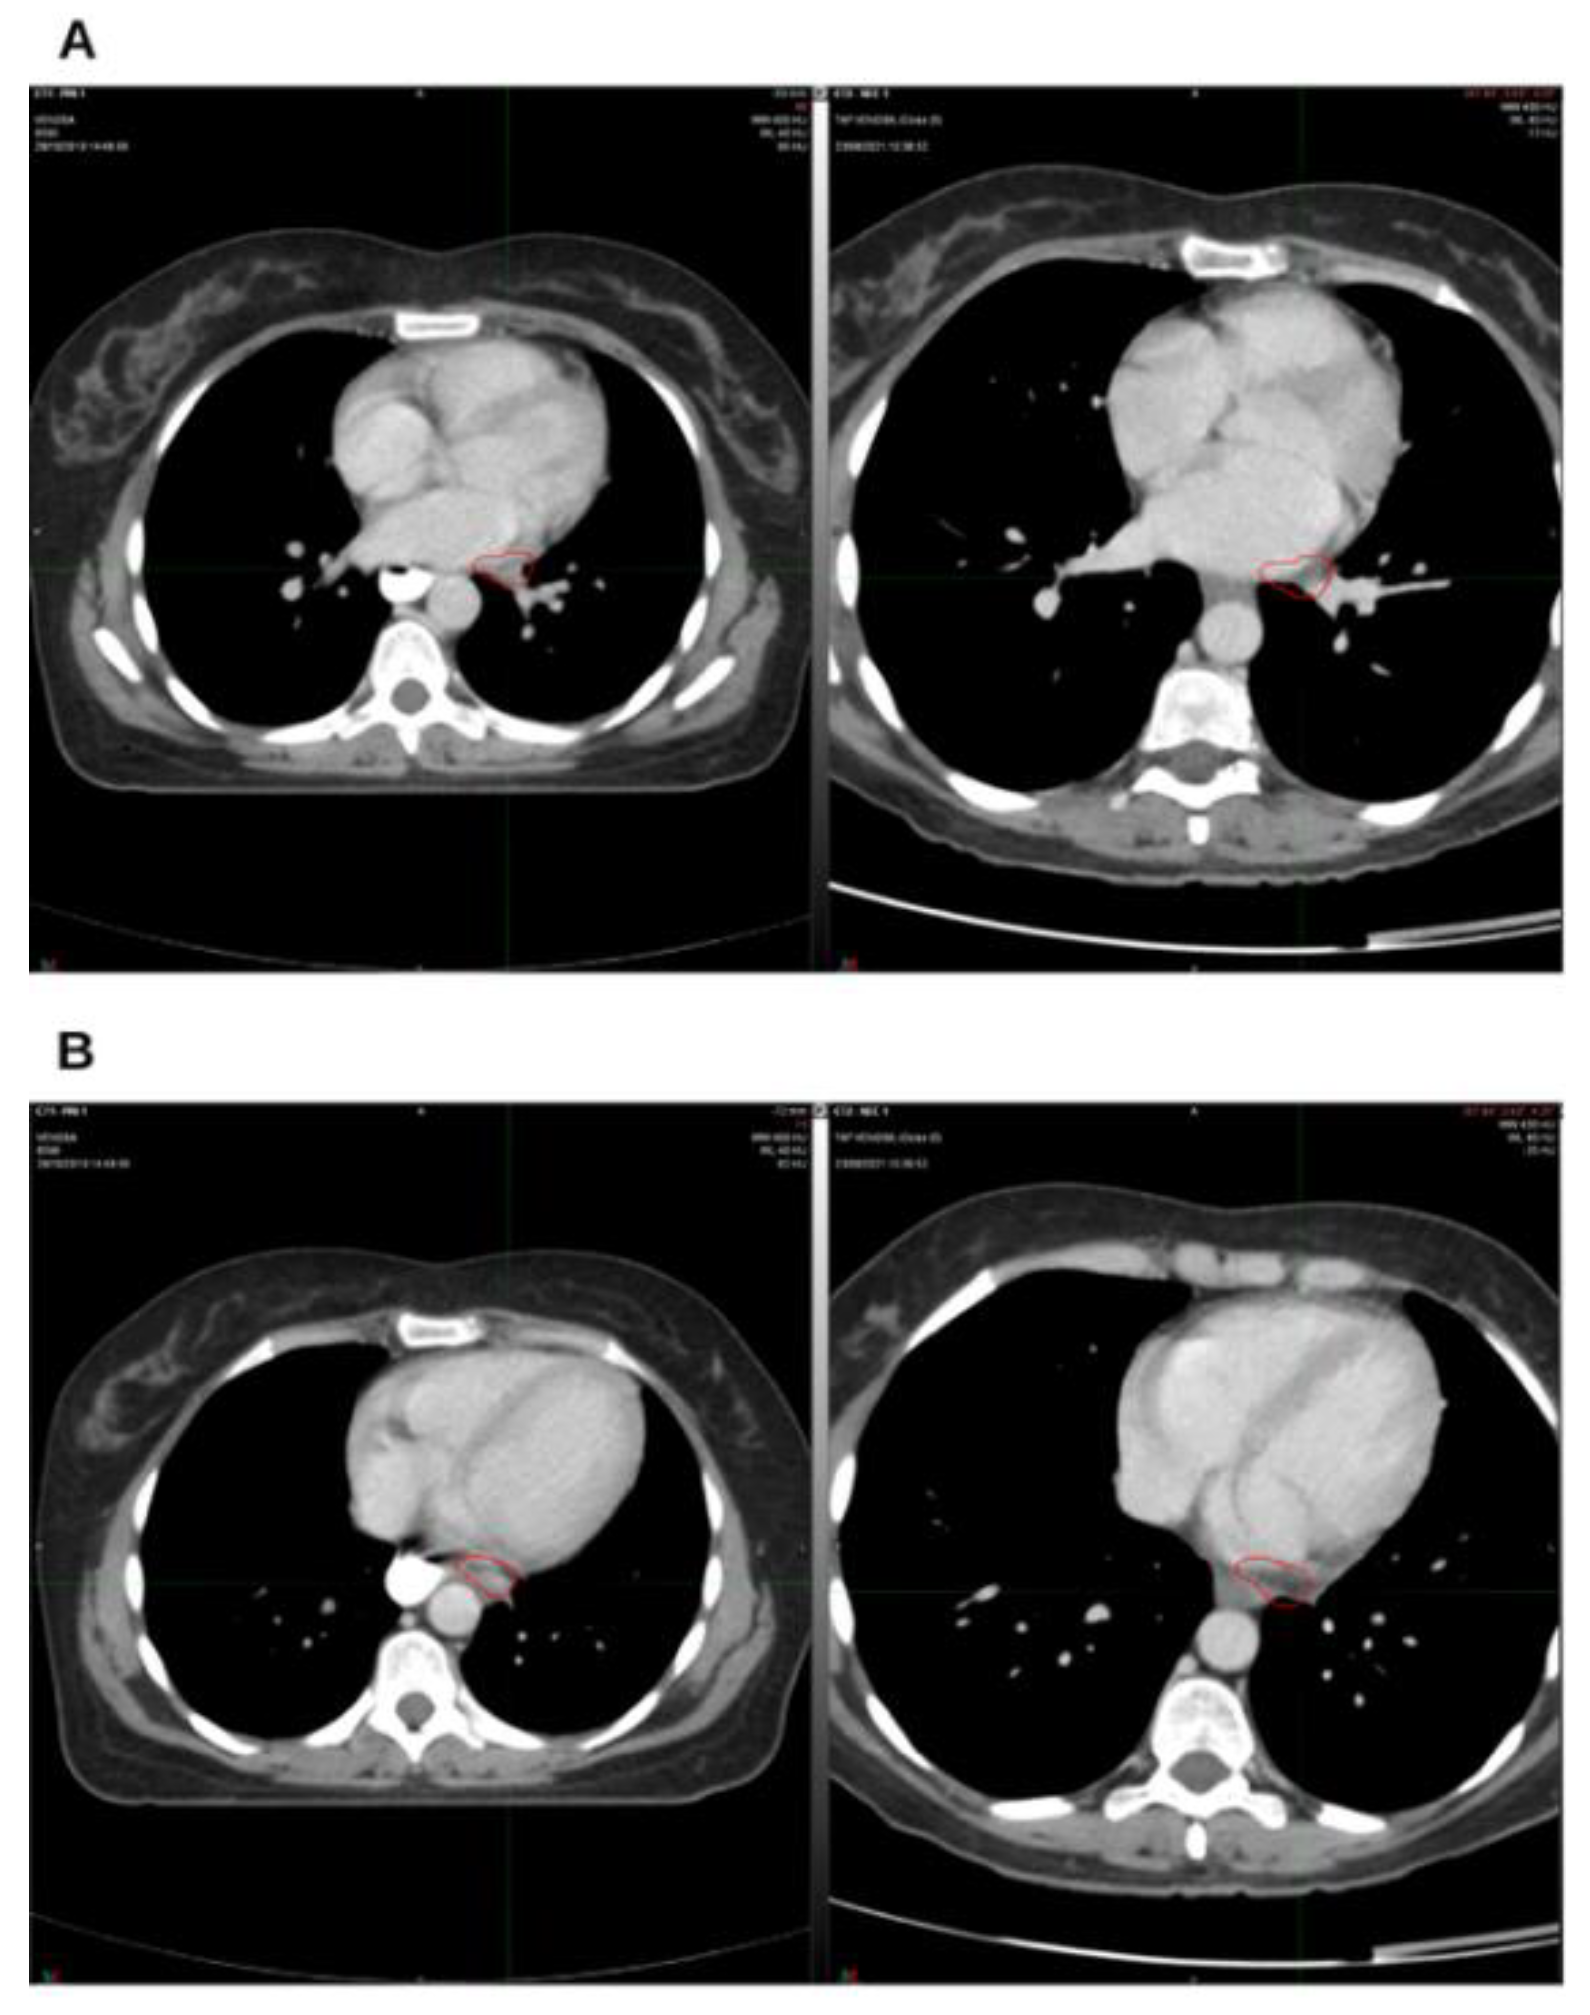

Background and Clinical Significance: Breast cancer is the most frequent malignancy in women. Advanced metastatic breast cancer is considered a treatable but incurable condition, with a median overall survival of only 2-3 years. Among its subtypes, triple-negative breast cancer (TNBC) accounts for a high proportion of breast cancer–related deaths. It is characterized by an aggressive clinical course, early recurrence, and a strong propensity for visceral and brain metastases. Case Presentation :We report the case of a Caucasian woman who, two years after being initially diagnosed and treated for TNBC, developed disease relapse with lung and mediastinal lymph node metastases. The patient received three months of chemotherapy combined with an adjuvant integrative protocol consisting of melatonin, cannabidiol, and oxygen–ozone therapy. This combined approach led to the complete disappearance of the lung nodules. Subsequently, stereotactic radiotherapy was performed and, in association with the ongoing integrative treatment, resulted in a significant reduction of mediastinal adenopathy. Introduction of immunotherapy, supported continuously by the same adjuvant strategy, achieved a complete and durable remission. Strikingly, the patient remained disease-free five years after the diagnosis of lung and mediastinal metastases. Conclusions: This clinical case highlights the potential benefit of using melatonin, cannabidiol, and oxygen–ozone therapy as part of an integrative approach in patients with aggressive metastatic TNBC. While it is not possible to establish causality from a single case, the sustained remission observed suggests that such unconventional adjuvant strategies could play a supportive role in enhancing the efficacy of standard oncologic therapies.